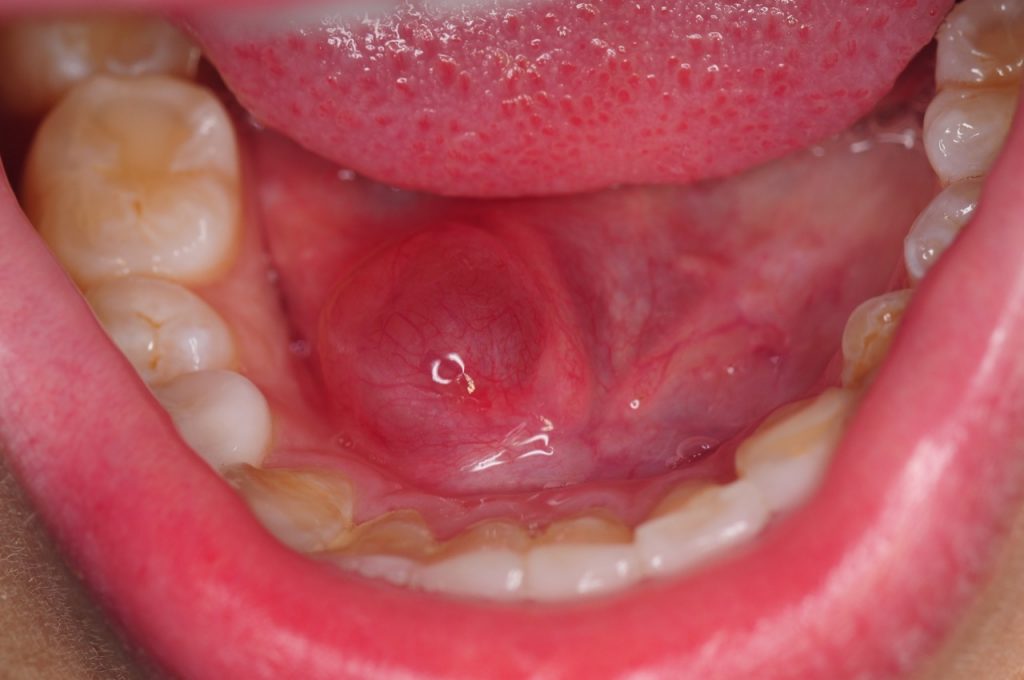

Marsupialization of Ranula- Floor of Mouth

This case report discussed management of floor of mouth ranula using marsupialization technique